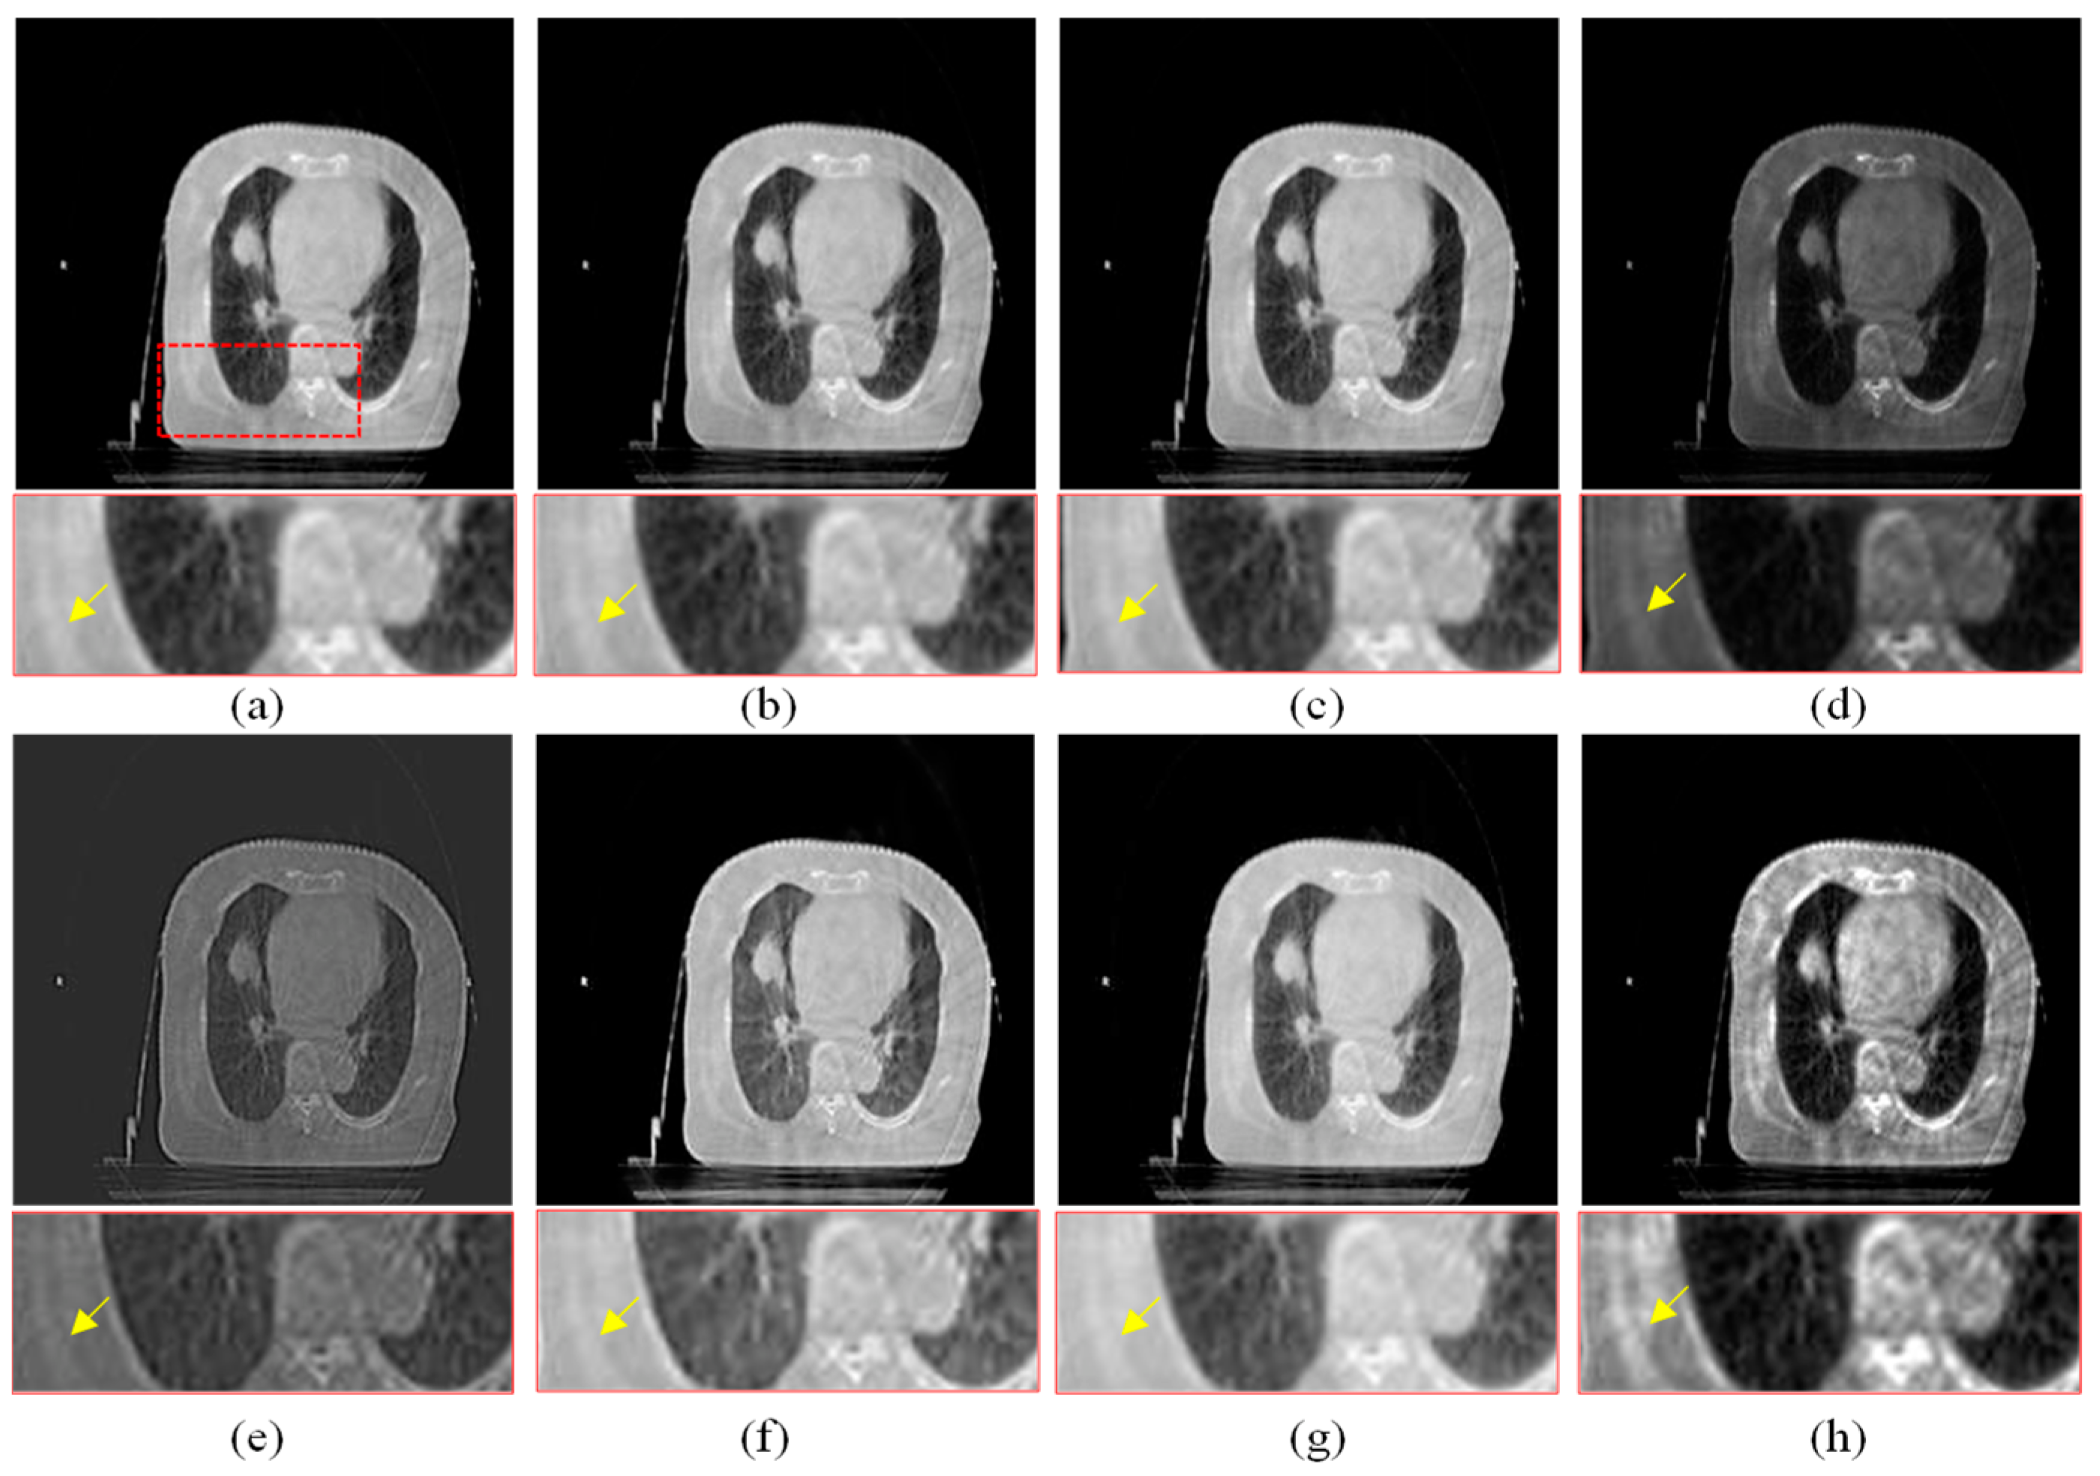

The visual comparison of different enhancement algorithms is shown in Figure 7, Figure 8, Figure 9 and Figure 10. Figure 7a is the source CBCT image, and Figure 7b is the image enhanced by MSR, which shows that the brightness of the source image is improved but with low contrast. Figure 7c,f,g show similar enhanced results with improved brightness but lacking in details. The DCP method improves the contrast of the source image, but does not enhance the details. As shown in Figure 7e, the CBF-based method shows good detail, but it still contains some noise. Compared with these methods, the proposed method shows better visual effects with higher contrast and richer detail, and the important regions are more significant.

Figure 7.

Enhanced results of pair 1. (a) Source CBCT images. (b) MSR. (c) MSRCR. (d) DCP. (e) CBF. (f) RRM. (g) SMIPC. (h) Ours.

Another three sets of experiments are shown in Figure 8, Figure 9 and Figure 10. As can be seen from the enlarged regions and the yellow arrows in Figure 8, it is difficult to directly observe the presence of skeletal information at this position from the enlarged region in Figure 8a. The enhancement results of the comparison methods also did not improve the visual contrast in this region, but the skeletal information can be clearly observed in our result, which means our results outperform the comparison algorithms in terms of detail, contrast, and visualization effect.

The same conclusion can also be obtained in Figure 9 and Figure 10. Especially in the enalrged region in Figure 10, our results provide a much clearer organizational structural and edge infromation, which is very helpful for disease diagnosis and treatment. Through comparison, it can be found that the rigidity informaiton in our results is more significant, the tissue edge in our results is clearer, and the contrast of the texture structure is also better than that of the comparison algorithms. The observation effect is greatly improved by our enhancement method, proving that our method can effectively enhance the CBCT images.